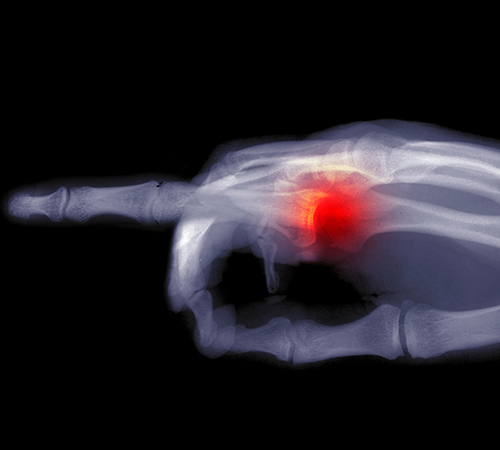

방아쇠수지

• 정상

• 방아쇠수지

손가락을 구부리고 펴는 것을 관장하는 굴곡건에 염증이 생긴 질환입니다.

손가락을 움직일 때 ‘딱’ 하는 마찰음이 난다고 하여 방아쇠 수지라고도 불립니다.

• 방아쇠수지 진단

손가락에 나타나는 통증 부위와 손가락을 쥐고 펼 때의 느낌 등

그 증상이 뚜렷하게 나타날 경우, 의료진의 의학적 검사만으로도 진단이 가능합니다.